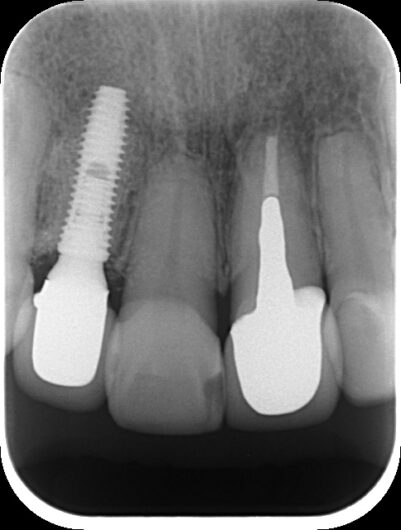

8年後の現在

「前歯の違和感」という主訴に対して、まずは客観的な評価が必要です。今回、以下の検査を実施しました:

- デンタルレントゲン撮影

- CT撮影

検査の結果、インプラント周囲の骨の状態、インプラント体の位置、周囲組織の状態など、すべてにおいて問題は認められませんでした。これは、8年間適切にメインテナンスを継続してきた成果と言えるでしょう。

長期メインテナンスの重要性

この症例から学べることは、定期的なメインテナンスと患者さんとの信頼関係の構築がいかに重要かということです。8年間という長期にわたり、問題なく経過しているのは、患者さんご自身の意識の高さと、継続的なケアの賜物です。